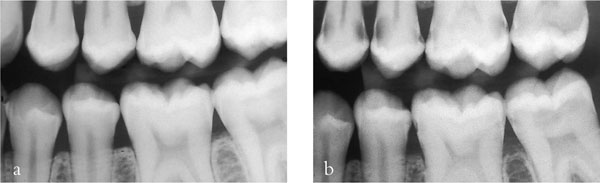

For a patient with new and secondary caries (Fig 1-5a,b) it is important that treatment is carried out in phases. The first phase should address pain and other immediate problems. Thereafter, care should be aimed at prevention. This stage of treatment should include stabilisation of the lesions and protection with temporary and transitional restorations. This is necessary to ensure that extensive lesions do not progress during the preventive phase of treatment. It also allows a stepwise approach to caries removal.

Fig 1-5 (a,b) A left bitewing radiograph of an 18-year-old patient (a), and four years later (b). This demonstrates that caries risk can change and the dentist should always be vigilant and continually assess risk. This patient’s initial treatment should be pain relief, followed by a stabilisation phase and prevention. Indirect restorations should not be considered until successful prevention has been instituted and caries risk has been controlled.